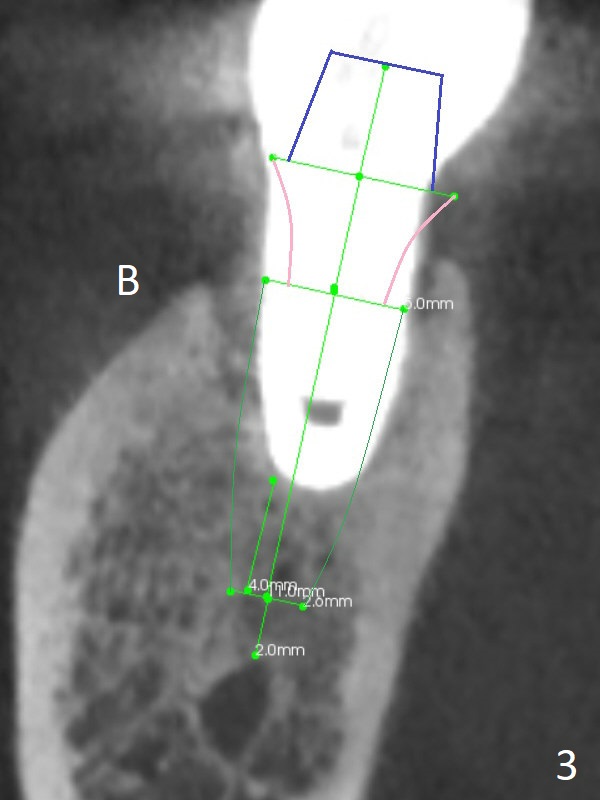

A 53-year-old woman has buccal gingival erythema and edema with deep pocket and purulent discharge. PA and CBCT show that the implant was placed distal and not deep enough (Fig.1,2) as well as buccal (Fig.3). When the failed implant is removed, try to place an implant mesiolinguoapically. Make purchase point/trough mesiolingual to the failed implant. Take PA with pilot drill for trajectory confirmation (Fig.1 red line). The implant will be 4 or 4.5 mm in diameter and 4 mm in the native apical bone. Use 1.6 and 3.8x11 mm Magic Drill until the lingual crest. Place PRF over the bone graft, Cyotplast buccally and provisional. Lower Molar Immediate Implant, Prevent Molar Periimplantitis (Protocols, Table), Armaments, #19 Xin Wei, DDS, PhD, MS 1st edition 12/10/2017, last revision 09/15/2020